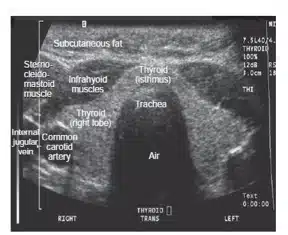

سونوگرافی تکنیکی است بر پایه امواج صوتی که تصاویر را به صورت Real Time  و بدون استفاده از اشعه ی یونیزان ایجاد می کند. در اولتراسونوگرافی از تکنیکی مشابه ولی امواجی با  فرکانس بالاتر از 20کیلوهرتز استفاده می شود. اسکنرهایی که برای اولتراسونوگرافی استفاده می شوند ایمپالس های الکتریکی ای تولید می کنندکه به وسیله ی یک Transducer  به امواج صوتی با فرکانس Ultra High  تبدیل می شوند. این امواج پس از برخورد با ساختار داخلی بدن دچار تغییراتی شده و سپس برگردانده می شوند. اشعه ی تغییر یافته ی برگشته، توسط همان دستگاه Transducer  دریافت و به انرژی الکتریکی تبدیل شده و در مانیتور نمایش داده می شود.